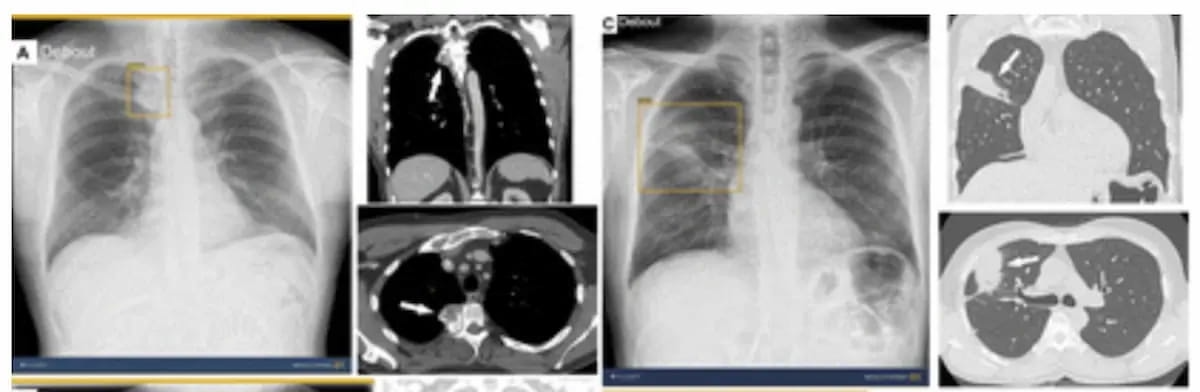

The Food and Drug Administration (FDA) has granted 510(k) clearance for ChestView, an artificial intelligence (AI)-enabled software, which may enhance detection of a variety of abnormalities on chest X-rays (CXRs).

Adjunctive use of the AI-powered software led to an average 38.6 percent increase in the detection of pneumothorax by general radiologists, according to a 2023 study.